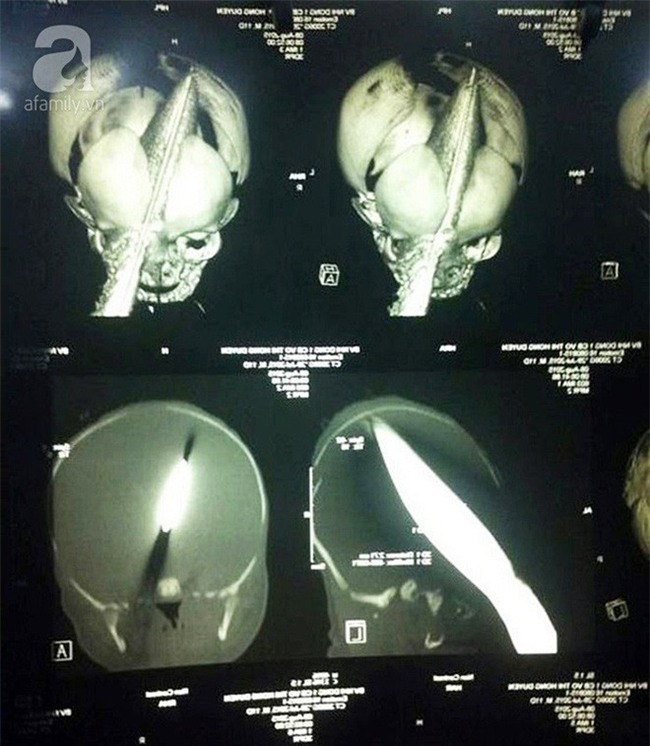

Một ngày của tháng 8/2015 khi mới 11 ngày tuổi, Phát bị một phụ nữ lạ mặt dùng dao đâm xuyên hốc mắt vào não trong bệnh viện. Tình trạng lúc ấy phải nói là "thập tử nhất sinh".

Nhưng bằng sức chiến đấu mạnh mẽ, trải qua nhiều ca phẫu thuật cam go, cậu bé từng bước hồi phục thần kỳ.